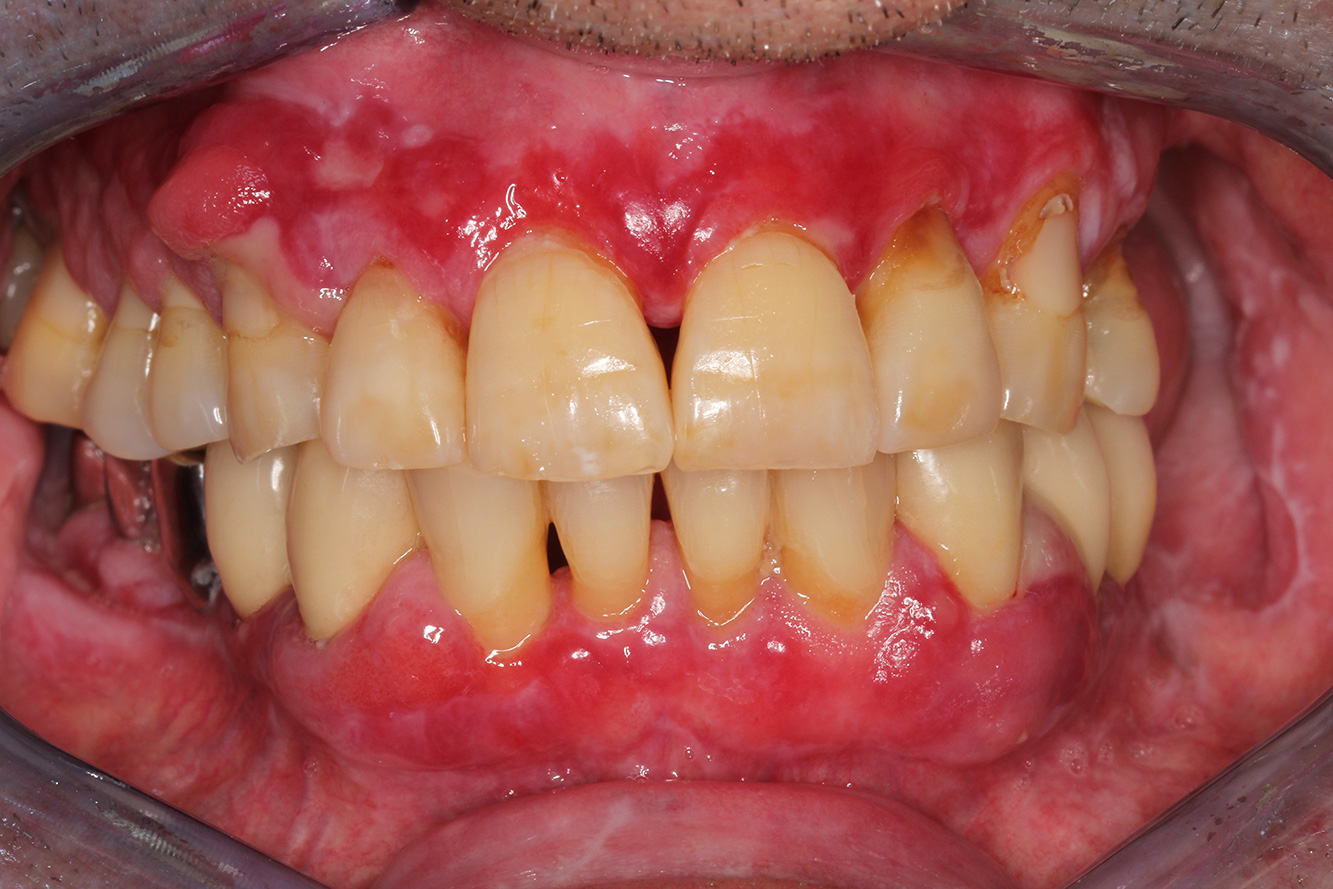

The transplant patient with gingival overgrowths

A 71-year old patient presents with having previously undergone a kidney transplant and with a history of hypertonia (high blood pressure). Due to his medical history, long-term medication with cyclosporine is required to suppress the immune system, as well as amlodipine to lower blood pressure. The patient also reports sensitive and bleeding gums. From an oral health perspective, the patient has undergone dental restoration and has eight missing teeth, pronounced gingival growth, and grade B, stage II periodontitis with active pockets and initial root caries on tooth 22. The caries risk assessment determines a moderate risk of caries (API 60). The following treatment recommendations can be determined for the prophylaxis session. more